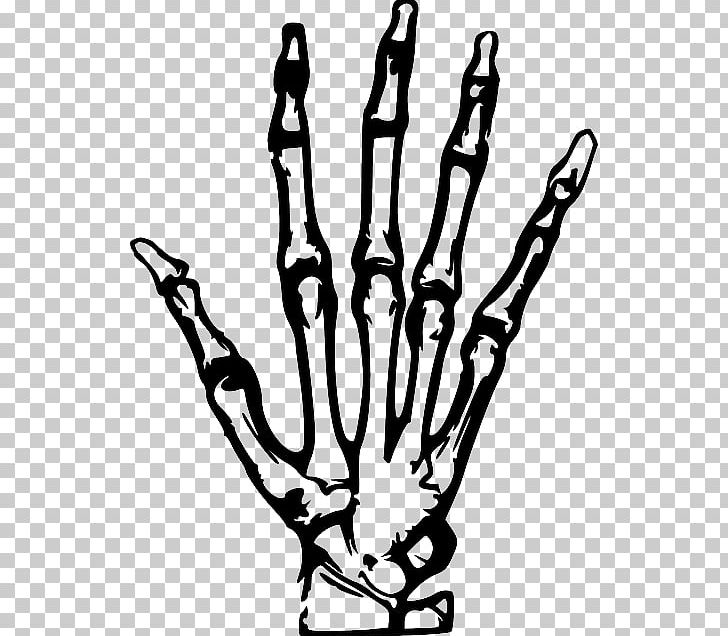

โครงกระดูกมือวาดไฟล์โปร่งใส | PNG Play 4 สาเหตุ “นิ้วเท้าเก” – โรงพยาบาลเวชธานี

รูปกระดูกมือจากโบราณสถานโดดเดี่ยวบนสีขาว PNG , กราฟิก, บน, การวาดภาพภาพ … ปวดข้อเท้าเกิดได้จากหลายสาเหตุ ทั้งอุบัติเหตุ การใช้งานเยอะ และโรคข้ออักเสบ

X-ray Hand PNG, Clipart, Black And White, Branch, Download, Finger … กระดูกหัก กระดูกแตก กระดูกร้าว สมานเร็วใน 1 เดือน ไม่ต้องผ่าตัด ปลอดภัย